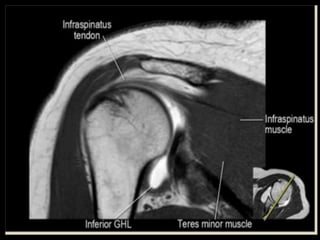

Shoulder

Joint.